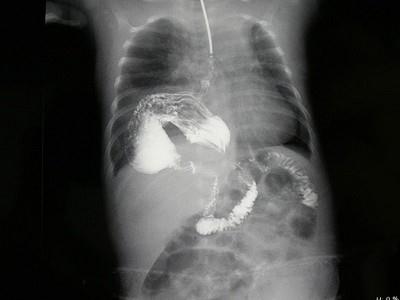

女,1岁,反复呕吐伴中度营养不良,结合影像,最可能的诊断为?(?)A.肺脓疡B.膈疝C.食道裂孔疝D.包裹性液气胸E.胃扭转

问题 女,1岁,反复呕吐伴中度营养不良,结合影像,最可能的诊断为?(?)

选项 A.肺脓疡 B.膈疝 C.食道裂孔疝 D.包裹性液气胸 E.胃扭转

答案 C